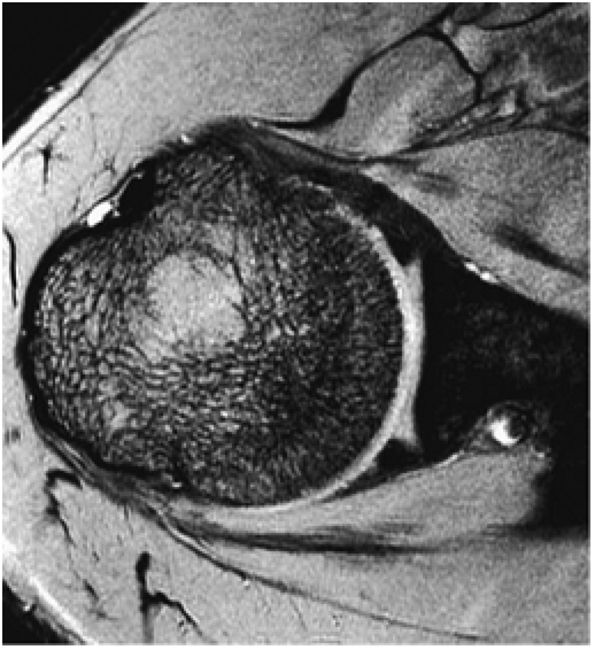

FIGURE 8.3 ● Glenohumeral joint contrast on axial T2* GRE image. Axial GRE images optimize visualization of intralabral signal and subscapularis tendinosis. FS FSE images are more sensitive to fluid collections, paralabral cysts, and articular cartilage.